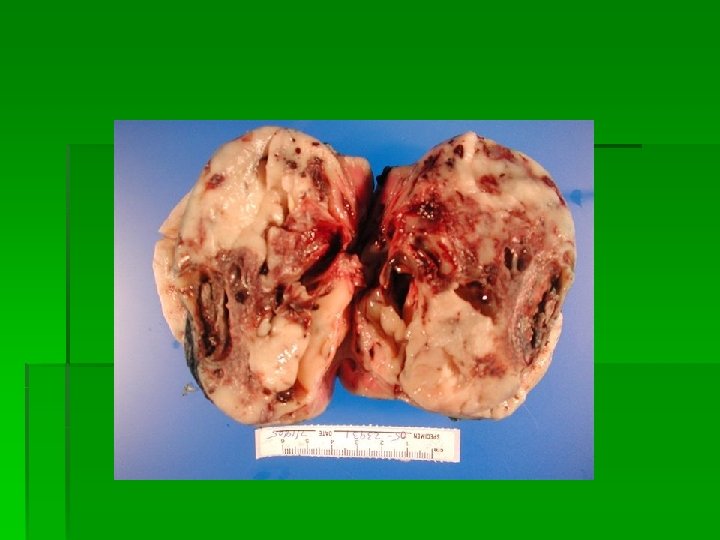

Solid Mass imprints § Cut mass in half § Blot dry § Need to remove blood/tissue fluid from surface § Use sterile gauze or other absorbent material § Excess blood/fluid inhibits cells from spreading and assuming normal size and shape § Touch the slide to the blotted surface § Stain